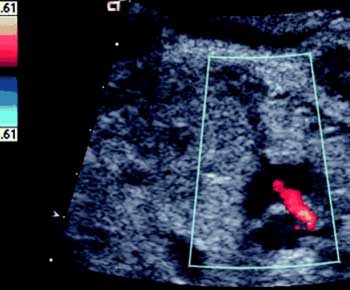

Sull’esempio del laboratorio digitale di ecografia dell’ospedale “Vito Fazzi” di Lecce, in funzione da oltre 7 anni annesso alle UU.OO. di Cardiologia-UTIC e di Cardiochirurgia e connesso in rete intranet con le UU.OO. di Medicina d’Urgenza/P.S., di Medicina, di Oncologia e di Ematologia, la Asl Le ha realizzato un laboratorio di ecografia di I livello negli ambulatori cardiologici territoriali.

Gli ambulatori territoriali ed ospedalieri sono stati dotati di un'infrastruttura infotelematica costituita da server, stazioni di lavoro informatiche collegate con ecocardiografi per la refertazione digitale in rete e per la condivisione di un archivio per referti ed immagini ecocardiografiche.

Il laboratorio centralizzato di ecocardiografia dell’ospedale “Vito Fazzi” di Lecce assume un ruolo centrale nell’ambito della rete in quanto, già dotato di stazioni di elaborazione e refertazione multiple, svolgerà funzioni di second opinion e teleconsulting per l’indicazione ad esami di secondo livello, ad interventi di cardiochirurgia o di cardiologia interventistica.